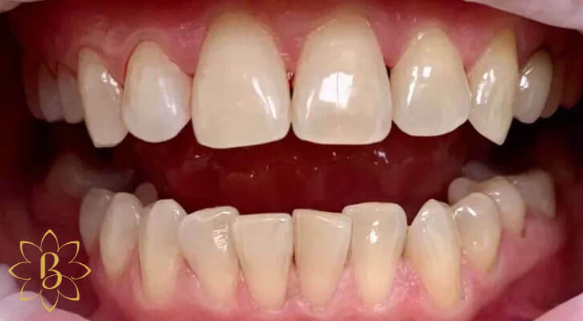

На странице представлено портфолио стоматологий Санкт-Петербурга с работами до и после профессиональной чистки зубов. В нашем портфолио собраны разные клинические случаи: от удаления незначительного налета до снятия массивного поддесневого камня. Здесь вы можете увидеть, как возвращается естественный цвет и внешний вид зубов после процедуры. Изучите результаты до и после чистки зубов, чтобы увидеть реальный эффект и выбрать клинику в Санкт-Петербурге, где профессиональная гигиена поможет вернуть зубам здоровый вид.

Профессиональная гигиена особенно важна при ортодонтическом лечении, ведь в повседневной жизни, дома, очень сложно поддерживать должный уровень гигиены полости рта! Даже если вы используете ирригатор и специальные ёршики! В нашей рубрике «до/после» вы видите то, что может быть с зубами при лечении брекетами, если не проводить своевременную чистку у врача-стоматолога. Марухно Дарья Александровна провела профессиональную чистку в несколько этапов, чтобы вернуть пациентке белизну ее собственных зубов! Брекет-система была поставлена не в нашей клинике, и почему пациентка не обратилась за профессиональной помощью раньше-вопрос) Но в данном случае, главное – итог! Кровоточивость после даже обычной чистки в такой клинической ситуации – естественный результат. Ведь обильный зубной налёт и зубной камень вызывают воспаление дёсен в виде гингивита, а порой даже пародонтита.